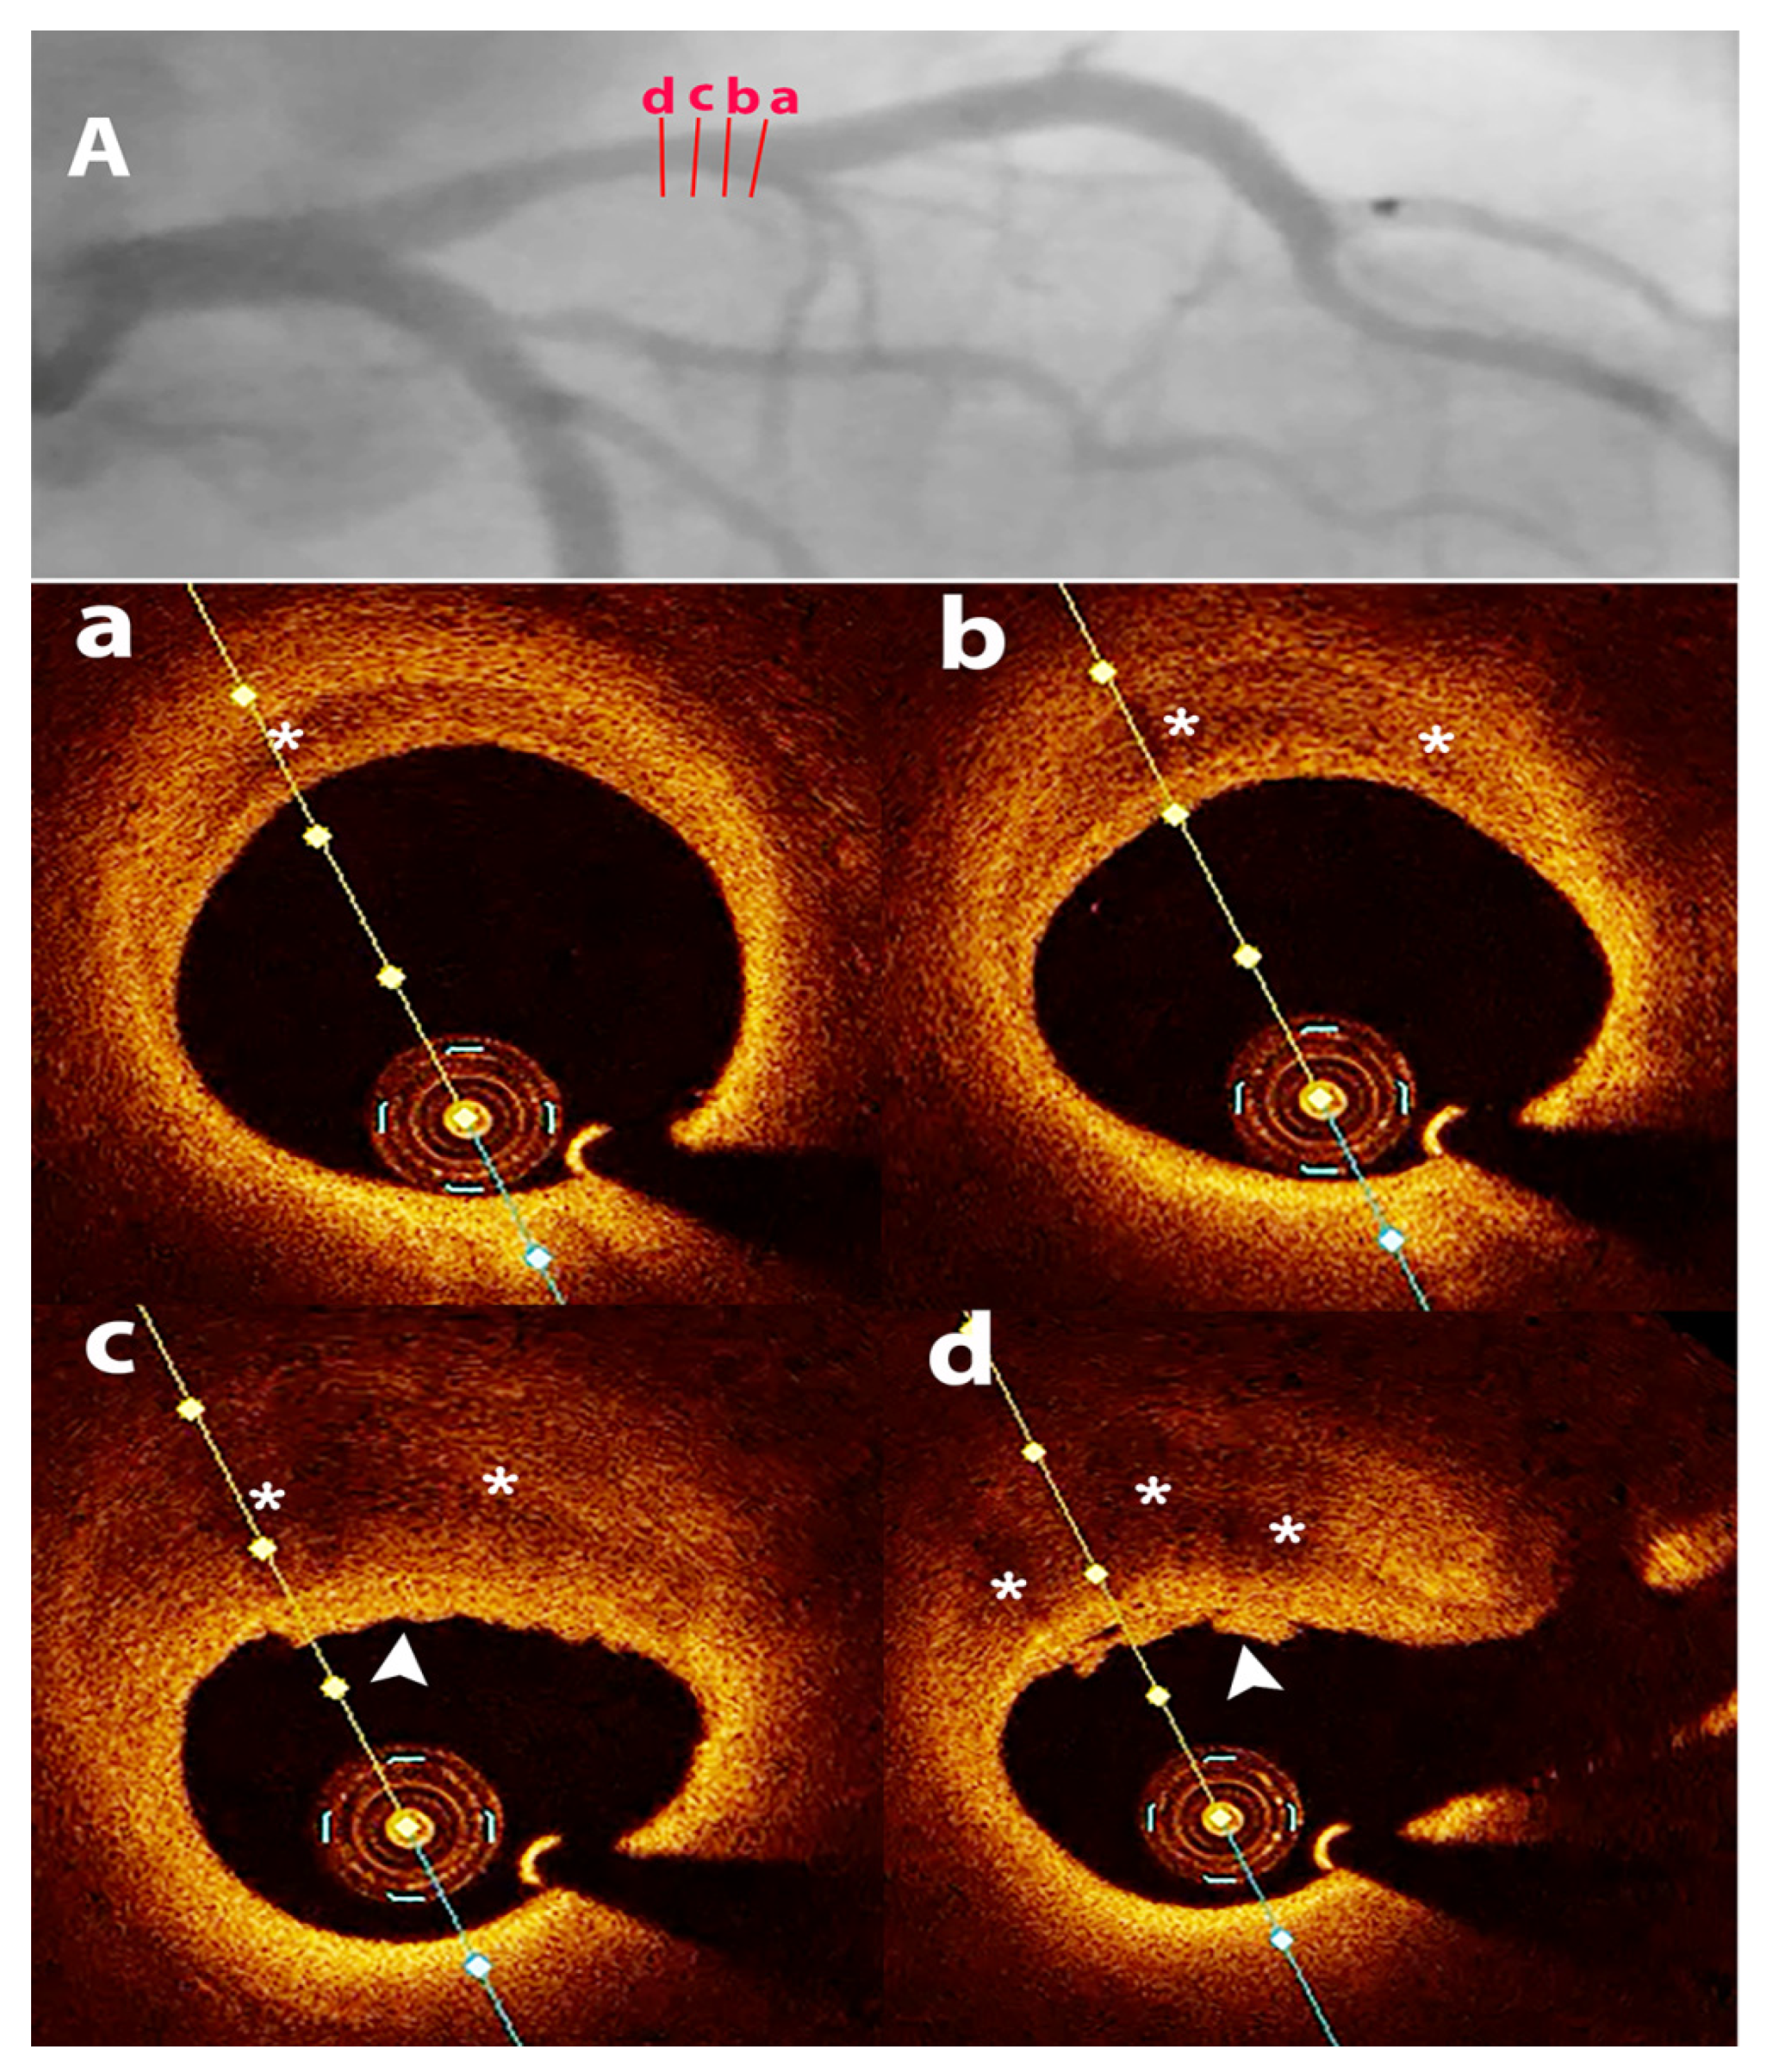

3.5.2. OCT in SCAD

OCT in SRCT